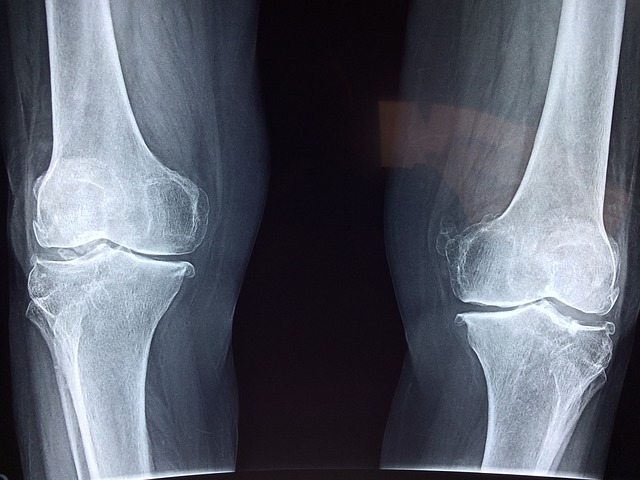

성상철 의학박사는 무릎 인공 관절 수술은 수술 2~3개월 후면 통증이 많이 없어지고 정상적인 생활이 가능해져서 환자들이 매우 만족해한다고 합니다. 최근 미국에서는 1년에 100만 명, 우리나라에서도 1년에 10만 명 정도의 퇴행성 관절염 환자가 인공 관절 수술을 받고 있으며, 대부분 연령이 65세가 넘는 분들이라고 합니다. 우리나라 의학 수준은 세계 최고의 수준으로 수술 환자의 만족도가 90~100% 가까운 안전하고 보편적인 수술이라고 하는대요. 연령이 많을수록 수술에 대한 두려움이 클 수도 있지만 큰 질병만 없으면 수술 후 회복 하는데 큰 문제가 없어 가벼운 운동이나, 사회적 활동이 가능하다고 합니다.